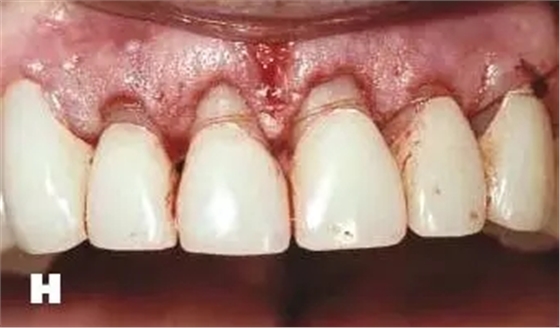

牙周炎發(fā)展到一定階段時(shí),僅采用基礎(chǔ)治療難以取得較好療效,必須通過適時(shí)而合宜的手術(shù)治療挽救患牙,才能保持牙周組織健康,延長患牙在口腔內(nèi)的壽命,維持牙列的完整性,促進(jìn)全身健康。其手段包括齦下刮治、根面平整、牙周翻瓣術(shù)、牙齦切除術(shù)、牙周夾板固定術(shù)等。

1、美容手術(shù):針對牙齦增生、影響美觀效果的患者,進(jìn)行牙齦的美容切除手術(shù),修整牙齦的形態(tài),恢復(fù)美容效果。

2、牙冠延長術(shù):在口腔修復(fù)治療中,一些患者的牙根條件略差,直接修復(fù)無法完成,需要通過牙周手術(shù)延長牙冠,創(chuàng)造修復(fù)條件。